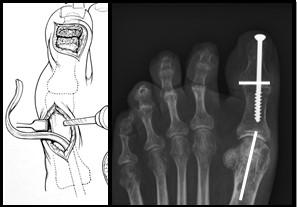

Extenderende Osteotomie 1e straal

Hierbij wordt de grote teen omhoog geplaatst door een botwigje uit te zagen aan de basis van de grote teen. Door dit wigje te verwijderen kan de grote teen omhoog komen waardoor de holling in de voet minder wordt. De voet wordt dus platter en beter belastbaar. Op de plaats waar we het botwigje hebben verwijderd plaatsen we een RVS schroefje en ijzerdraadje om het middenvoetsbeentje van de grote teen op de juiste positie te houden. Zodra het bot genezen is, is de schroef niet meer nodig en kan bij klachten evt worden verwijderd.

Figuur 4: Het bovenste linker plaatje is een schematische weergave van de “osteotomie”. Het driehoekje bij de pijl wijst naar de wig die uitgezaagd wordt. Het plaatje eronder laat de situatie zien na verwijderen van het wigje. Het middelste plaatje laat een voetfoto van een patiënt zien voor de operatie, de witte streep is de plaats van het litteken. het meest rechtse plaatje is na de operatie. Bij de pijl zie je de schroef en het ijzerdraadje om de botdelen op de juiste positie te houden.